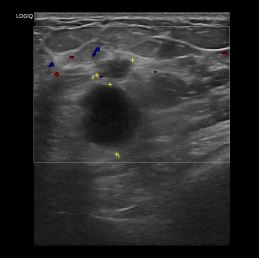

상기환자는 우측유방 만져지는 멍우리로 내원하신 50대 초반 여성분으로 의심스러운 우측 혹 조직검사 시행해 유방암 진단되었습니다.